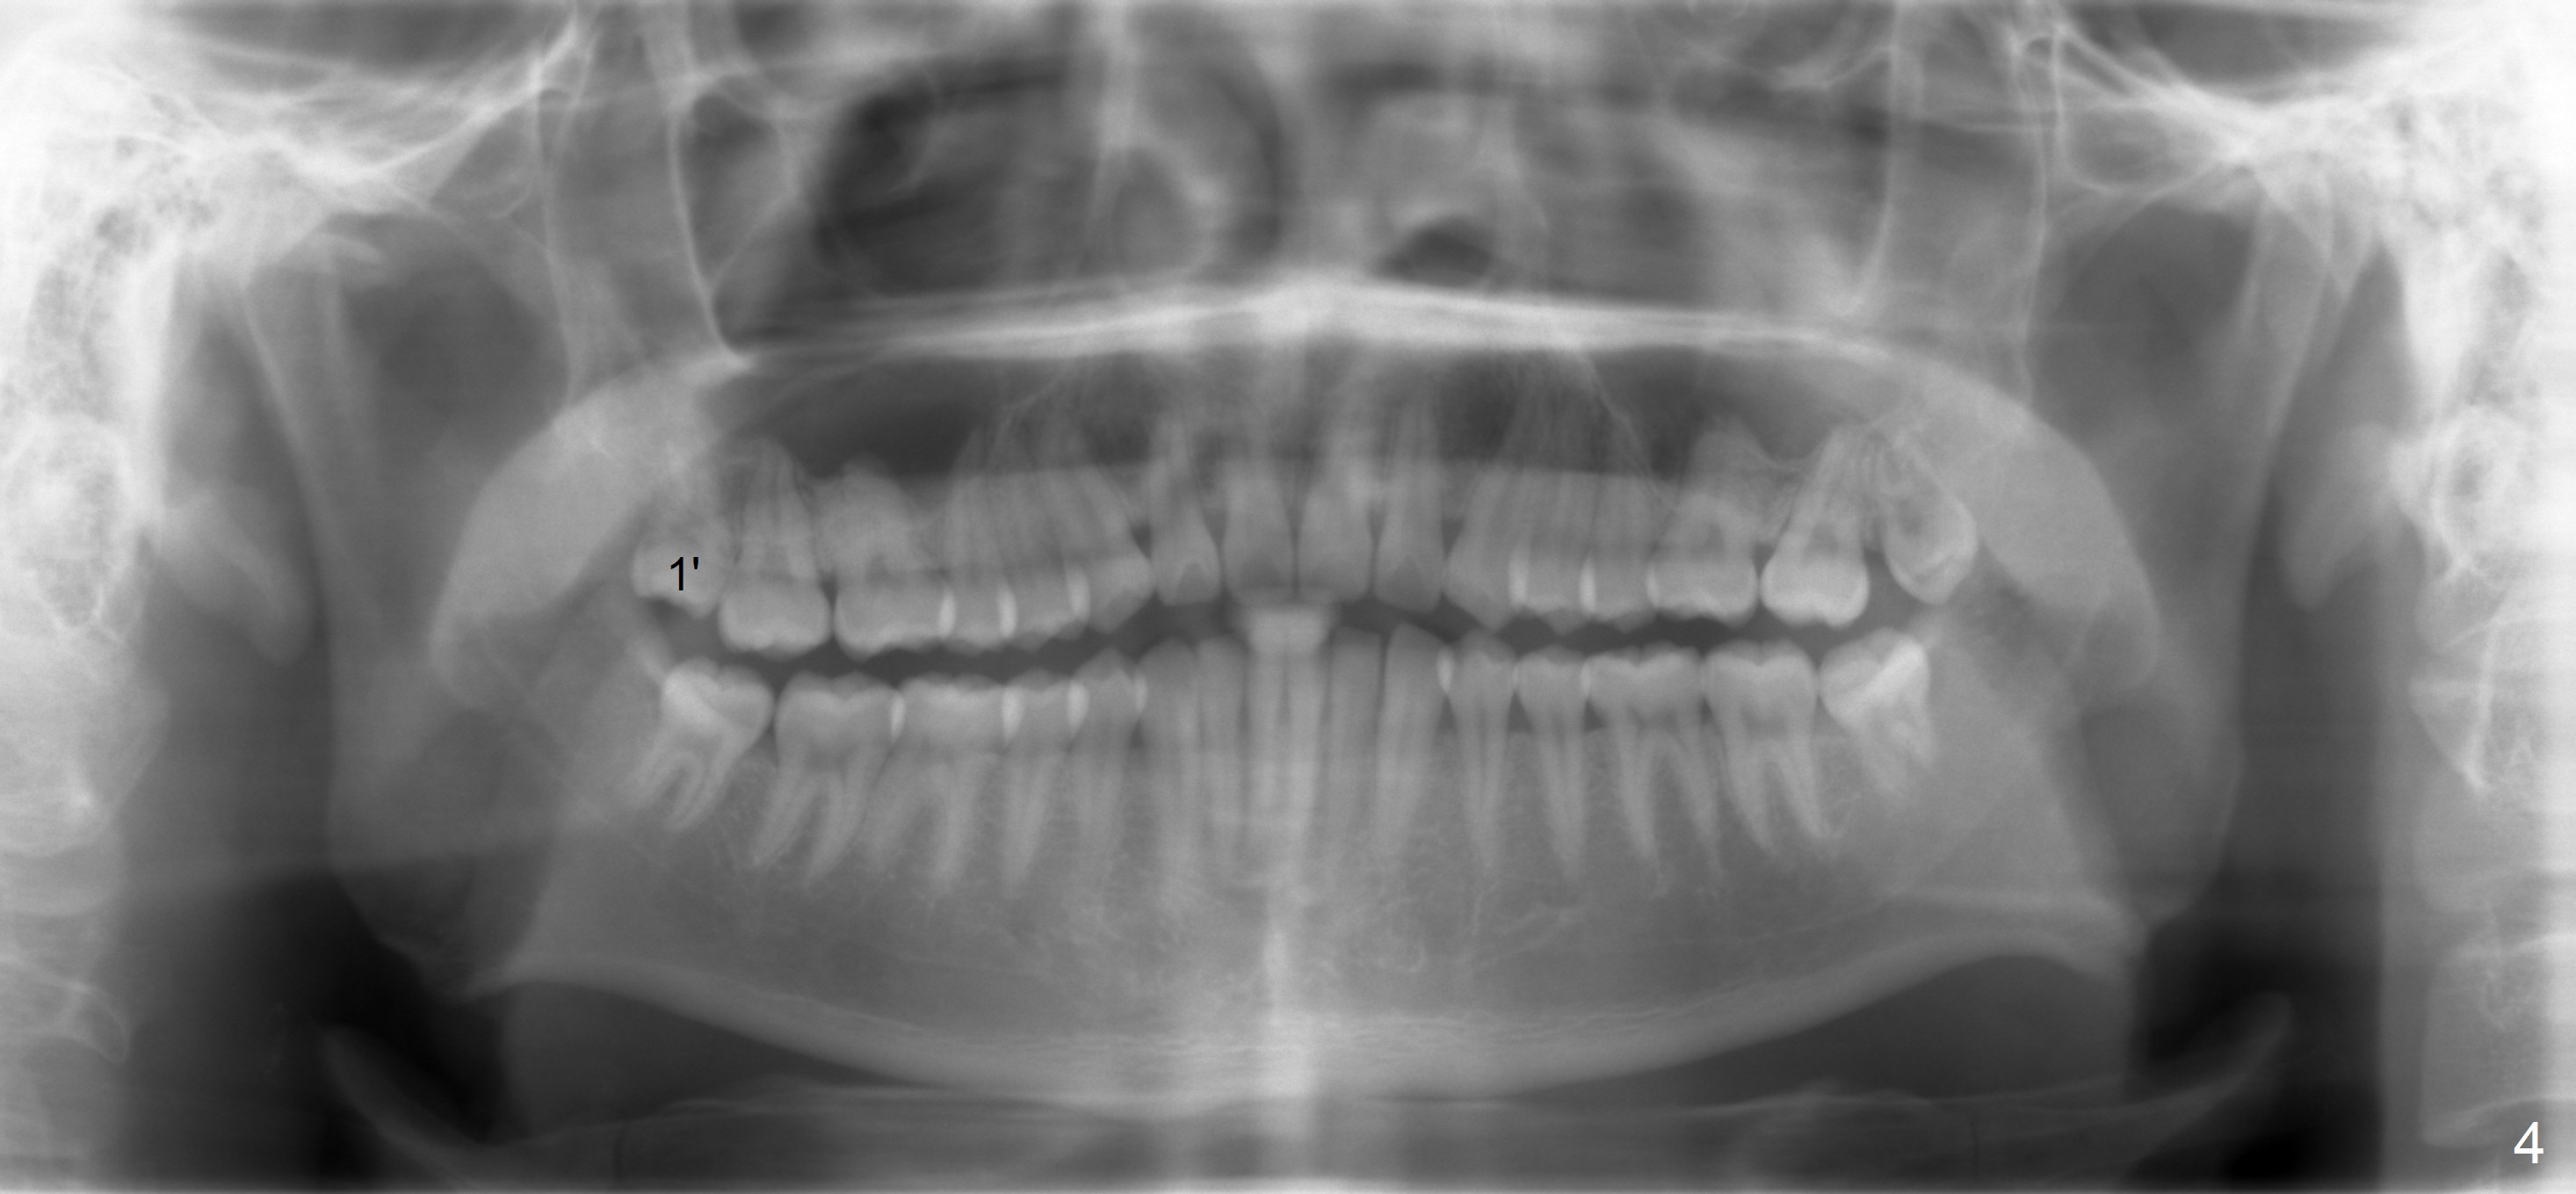

A 18 year old man has fully developing jaws.  It appears that there is enough room for 4 3rd molars to erupt normally.  In fact, the teeth #16,17,32 erupt.  Attached are pan taken 2 and 5 years ago (Fig.2,1, respectively).  I wonder whether we can take out one of the upper right 3rd molars and let the other erupt.  If the latter does not happen, #1 and 32 will be extracted.  The teeth #16 and 17 are not to be extracted.  Due to insurance limitation, the pan is not updated.  Thanks.

Panoramic X-ray is taken immediately post extraction of one of the upper right 3rd molars (Fig.3,3') and 20 months postop (Fi.4,4').  In fact the remaining one has erupted normally.